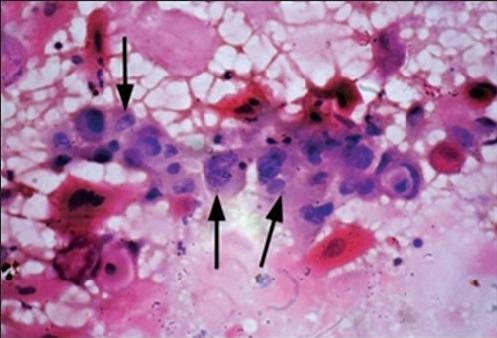

A total number of 55 patients of histopathologically proven oral cancer presenting with enlarged superficial cervicofacial lymph nodes were included in the study. Patients were subjected to clinical examination according to a specially designed proforma and the TNM staging was done. If more than one enlarged nodes were present, then the node with the largest diameter was chosen for further Doppler ultrasonographic examination followed by fine needle aspiration cytology test of the same node.

Correlations of patterns of color Doppler flow signals with cytological diagnosis showed that central type of vascular pattern was statistically significant parameter for benign lymph nodes and peripheral type of vascularity was highly significant parameter for malignant lymphadenopathy. It was found that the cut-off value of resistive index 0.6 was statistically significant in the assessment of metastatic node (P < 0.01) with a sensitivity of 45.5% and specificity of 93.9%. On comparison of the clinical features (TNM staging) with Doppler sonographic features, it was found that the characteristic features suggestive of malignant lymph nodes on Doppler sonography such as peripheral blood flow and high resistive index were more consistently and frequently associated with the higher sub-stages of T3 and T4 and N2b and N2c of TNM staging system.